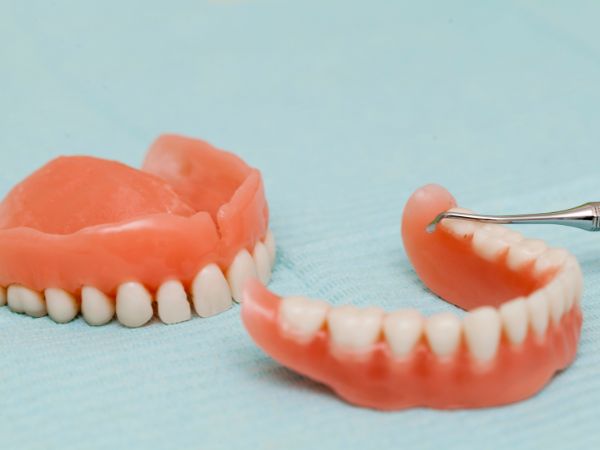

Las prótesis dentales son una excelente opción para reemplazar dientes perdidos y restaurar la función masticatoria y estética de la boca. Sin embargo, si la prótesis no se ajusta correctamente, puede causar diversos problemas, entre ellos dolor en el paladar. En nuestra clínica dental en Colina atendemos estas urgencias, por eso aquí te explicamos sobre el dolor en el paladar por prótesis dental que no está funcionando correctamente.

- Reemplazar la prótesis: Si la prótesis está demasiado desgastada o dañada, puede ser necesario reemplazarla por una nueva.